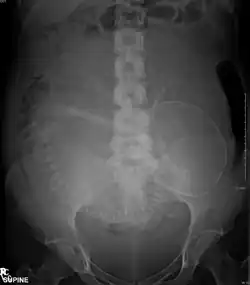

Projectional radiographs

Projectional radiography is the practice of producing two-dimensional images using X-ray radiation. Bones contain a high concentration of calcium, which, due to its relatively high atomic number, absorbs X-rays efficiently. This reduces the amount of X-rays reaching the detector in the shadow of the bones, making them clearly visible on the radiograph. The lungs and trapped gas also show up clearly because of lower absorption compared to tissue, while differences between tissue types are harder to see.[115]

Projectional radiographs are useful in the detection of pathology of the skeletal system as well as for detecting some disease processes in soft tissue. Some notable examples are the very common chest X-ray, which can be used to identify lung diseases such as pneumonia, lung cancer, or pulmonary edema, and the abdominal x-ray, which can detect bowel (or intestinal) obstruction, free air (from visceral perforations), and free fluid (in ascites). X-rays may also be used to detect pathology such as gallstones (which are rarely radiopaque) or kidney stones which are often (but not always) visible. Traditional plain X-rays are less useful in the imaging of soft tissues such as the brain or muscle. One area where projectional radiographs are used extensively is in evaluating how an orthopedic implant, such as a knee, hip or shoulder replacement, is situated in the body with respect to the surrounding bone. This can be assessed in two dimensions from plain radiographs, or it can be assessed in three dimensions if a technique called '2D to 3D registration' is used. This technique purportedly negates projection errors associated with evaluating implant position from plain radiographs.[116]